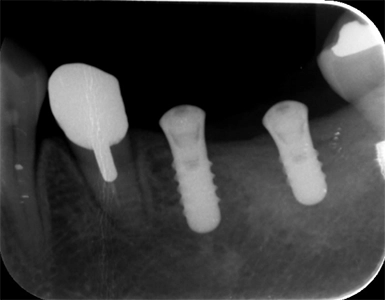

抜歯窩保存術 インプラント埋入術

初診時

左下7抜歯時

骨造成4か月後

インプラント手術後

年齢・性別 55歳・女性

主訴 左下の奥歯より嫌な匂いがする

診断名 左下第二大臼歯 歯根破折、慢性根尖性歯周炎

治療内容 左下7の歯根破折に起因する慢性根尖性歯周炎により抜歯が必要となった。患者様は機能性と審美性の回復を強く希望したため、抜歯後骨造成を行いインプラント治療を行った。

(GBR:歯根破折の炎症により、抜歯窩周囲の骨吸収が進んでおりこの状態ではインプラントを安定して埋入するだけの十分な骨量がないと判断し、GBR(骨造成)を行った。)

インプラント体と骨が強固に結合するまで通常3~6か月の治癒期間を設るため、インプラント体を埋入し、3か月経過後骨との結合を確認した後、型取りを行い仮歯で問題ないことを確認し、セラミックの人工歯(上部構造)を装着して治療完了した。

治療期間 インプラント埋入前に中断があったため1年7か月→初診からインプラント治療完了まで

費用 骨造成:110,000円

インプラント2本:902,000円(1本の場合は544,500円)

リスク・副作用 術後の痛み、腫れ、出血が出ることがある

感染の可能性、腫れや再生不良が起こることがある

喫煙や清掃不良、炎症が重度の場合は組織再生の効果が十分得られないことがある